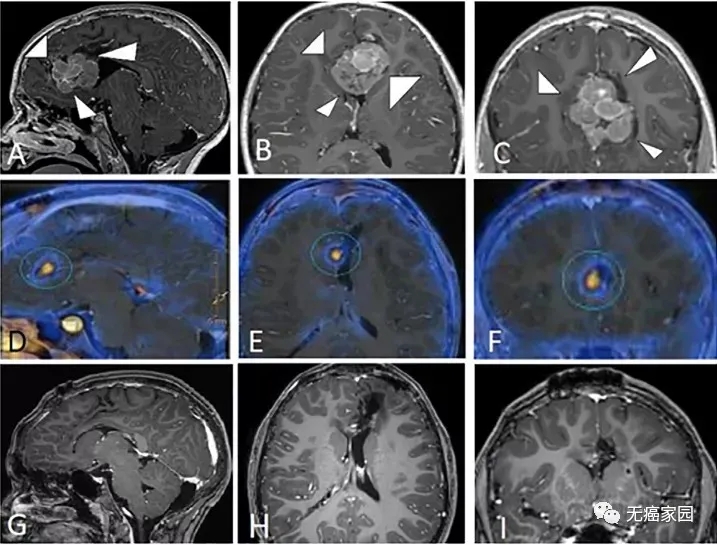

7岁男孩确诊非典型脑膜瘤,质子治疗后肿瘤明显减小,近3年无复发,且认知发育正常

7岁男童,反复出现严重的头痛发作,伴有跌倒、震颤和尿失禁,后被确诊为非典型脑膜瘤(WHO II级),Ki67增殖指数为18%。曾实施两次手术,并于术后45天进行质子治疗。患儿对质子治疗耐受良好,除治疗区域的部分脱发外,未观察到毒性(即神经系统症状)。

A~C显示患儿最初脑内的额叶占位,并伴有病灶内出血。D~F显示患者第二次手术后脑内仍有残余肿瘤,G~I显示质子治疗后肿瘤消失90%,近3年未见复发。